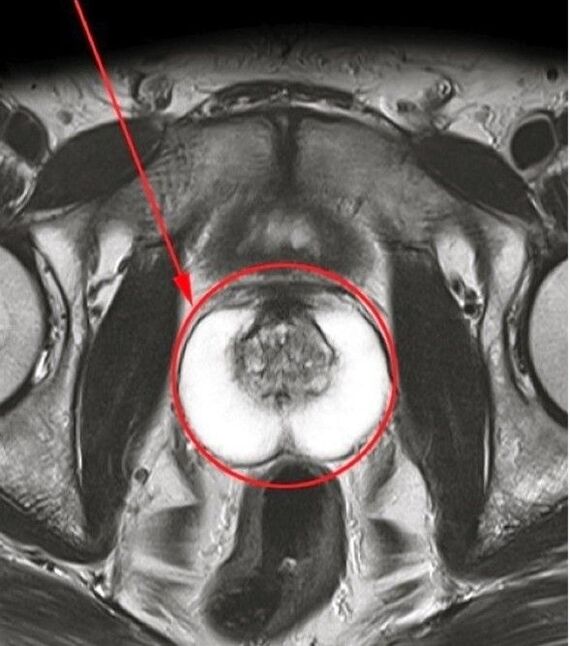

Ich wandte mich dem Arzt zu und verstand die Bedeutung der rechtzeitigen Behandlung. Basierend auf den Ergebnissen der Untersuchung wurde bei mir chronische Prostatitis diagnostiziert. Der Spezialist empfahl, dass ich eine Behandlung mit einem natürlichen Arzneimittel unterziehe Predstonorm In Kapseln.